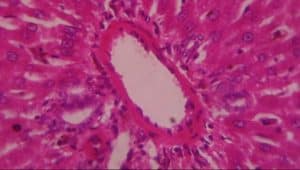

Figure 10: Liver (control) composed of A-hepatocytes, B-sinusoids, C-portal vein and D-bile duct (H&E x 400)

In group III (lead only), the histological evaluation (Figure 6) demonstrated vascular ulceration, vascular congestion, intense necrosis of major liver architecture, and periportal inflammation, further confirming the toxicological effect of lead on the liver. The above histological finding corroborated earlier work done by[26,27,28,29] on vascular congestion of the liver architecture[30] on necrosis of the liver architecture and on the vascular ulceration and periportal inflammation.[31]